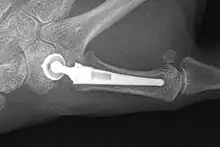

Joint Replacement

There are several prostheses available for use although they have not been widely successful. The goal is to create a stable artificial joint by replacing the old affected joint with new material. Newer prostheses tend to have better results than older ones.[27] Prostheses come in many varieties, such as spacers or resurfacing prostheses.

The total CMC1 joint replacement is a newer arthroplasty which has developed into a cemented and a non-cemented design. The cement acts as a binding factor for fixation of the prosthesis to the host bone. The non-cemented procedure is a good option to treat stage II and III OA and could be better on short-term than the trapeziectomy with LRTI. However, on the longer term, literature indicates the contrary.[27]

Overall, joint replacements are related to long-term complications such as subluxation, fractures, synovitis (due to the material used) and nerve damaging.[35] In many cases revision surgery is needed to either remove or repair the prosthesis. Also note that usage of a joint replacement is heavy in costs.

The quality of the prostheses is improving and there is reason to believe this will have a positive effect on outcome in the years to follow.[27]